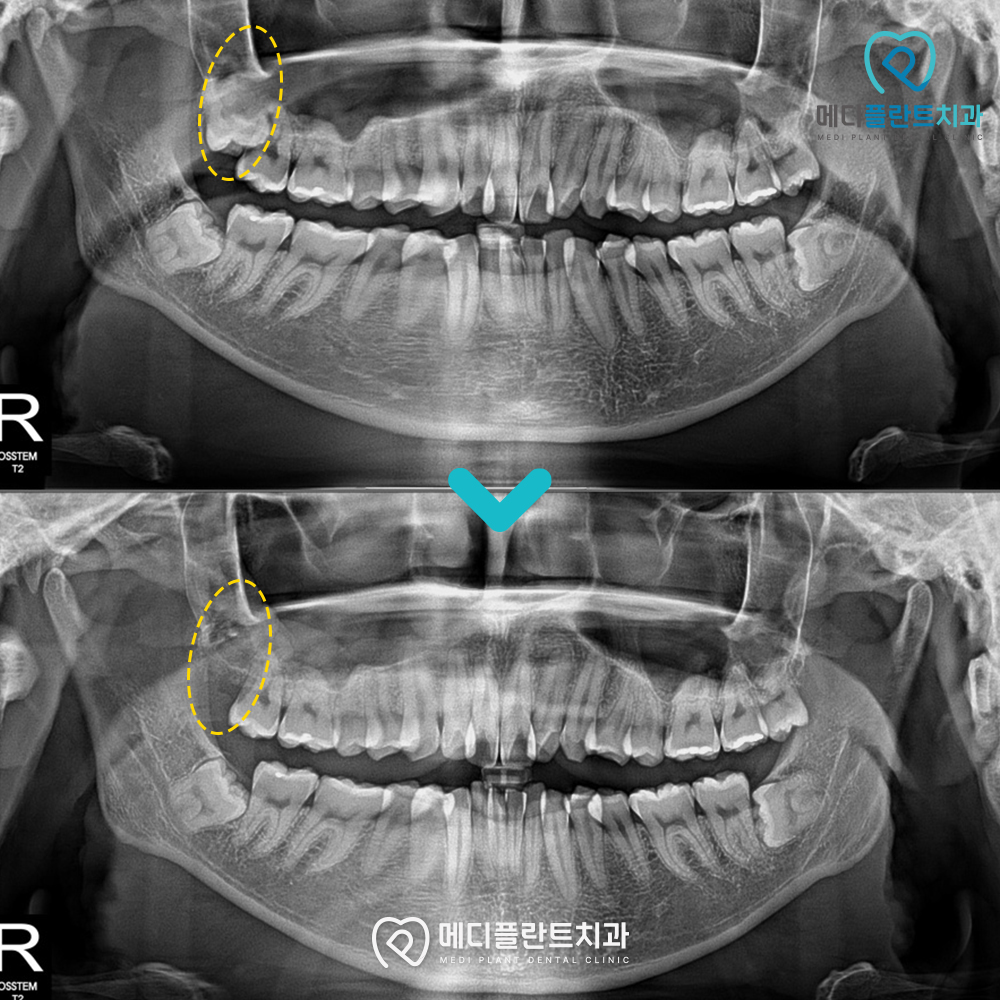

진료를 받으신 분의 사례를 소개해드겠습니다.

환자분께서는 사랑니 통증 때문에 오랜 고민 끝에

후석로치과 메디플란트치과를 찾아주셨습니다.

방사선 촬영 결과

사랑니가 잇몸 속에 매복되어

비스듬히 자라고 있었고,

옆 치아를 눌러 반복적인 염증이 생기면서

통증이 심해 일상생활에도

불편을 겪고 있는 상태였습니다.